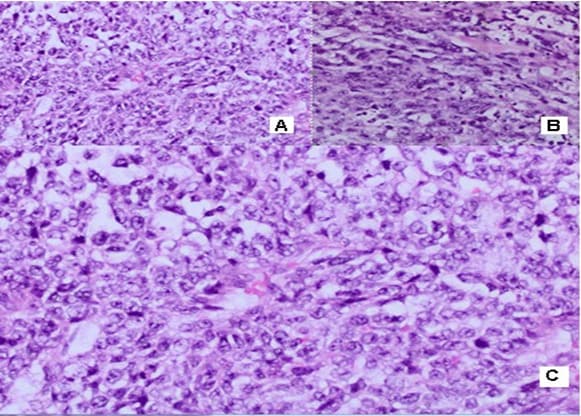

in the left inguinal region, two subcutaneous nodular formations with a heterogeneous structure and a maximum size in the axial plan of 58mm/43 mm are visualized. The borderline fat is deleted against m. Sartorius. No data on enlarged pelvic lymph nodes. Surgery/05.01.2022: When opening the subcutaneous fat, the tissues are thickened with the leakage of purulent secretions. A formation was found with a diameter of about 5cm/5.5 cm with the soft consistency, tightly coated with the underlying tissues and vessels and with decay data. Tumor excision and necrectomy were performed. Histological Result: Macroscopic description irregularly shaped material, crumbly, 5cm/3cm/3cm, with soft consistency, a colorful cut surface with brownish gray-rounded areas. Morphological Result: Soft tissue infiltrated by a solid tumor with highly atypical cells with polymorphic nuclei with coarse chromatin, visible nucleoli, frequent mitotic figures, scarce predominantly eosinophilic cytoplasm. Consultation of an experienced pathohistologist: Soft tissue material with tumor infiltration with a predominantly solid construction, focal with pseudopapillary growth around blood vessels, necrotic areas and bleeding. The tumor is made up of cells with moderate to pronounced nuclear polymorphism with prominent nucleoli, eosinophilic cytoplasm, high mythotic activity, stroma richly vascularized with the presence of mature lymphocytes and lymphoid tissue around the periphery (Figure 1). Immunohistochemical (IHC) Analysis: HMB45 (-), CK7 (-), CK20 (-), GATA (-), CD30 (-), PLAP (-), PAX8 (-), PSAP (-), TTF (-), Podoplanin D2-40 (-), Oct3/4 (-), Alfa FP (-), HCG (-). CD117 focal positivity, CD20 (+) in lymphoid tissue. IHC analysis excluded malignant melanoma, metastasis from adrenal carcinoma, germinative cell tumors of the testis, renal cell carcinoma, prostate and urinary carcinoma, lymphoma, lung carcinoma metastases, hepatocellular carcinoma metastases. Conclusion: It is about tumor infiltration from an extremely undifferentiated malignant tumor. After 1 month of the CT with contrast, in the left inguinal region a subcutaneous nodular heterogeneous formation with positioned dren and single air collections in the structure are visualized. Maximum size 66/57 mm. Deleted border adipose tissue compared to m. Sartorius, peripheral nodular lesions with a slight increase in density through the phases of examination, with increased density of adipose tissue. No data on enlarged pelvic lymph nodes. Surgery/28.02.2022: A 7cm/8cm tumor, tightly fastened with fascia Lata and Sartorius muscle and Adductor longus muscle was established. The fascia Lata was cut to the top of the Scarpa triangle. The whole preparation, along with the fascia and part of the muscle fibers of the two muscles, were prevented to the presentation of the artery and vein femoralis.

The whole preparation, along with the adipose tissue, fascia and surface and deep lymph nodes, are removed. Histological Result: Macroscopic skin 13 cm/4.5 cm with underlying soft tissues. In the subcutaneous fat, a tumor formation of 8cm/6.5cm/3 cm is found. The tumor has extensive zones of necrosis and hemorrhage, with focal areas of brownish pigmentation on the periphery, solid construction with a grayish color, lobulated, relatively distinguished from the surrounding tissue. The resection line at the bottom of the removed material is focally engaged. Morphological Result: Soft tissues with infiltration of hypercellular

malignant tumor with fascicular structure, in places with the arrangement of „fish bone“, with hemorrhage and geographical type of necrosis, perivascular hypercellularity (Figure 2). Cytologically, the tumor is represented by spindle shaped cells with hyperchromic and wavy nuclei, coarse dispersed chromatin, identified nucleoli, eosinophilic cytoplasm, ranging in quantity to extremely scarce, high mitotic index 46 mitoses per 10 (Figure 3). Eight lymph nodes without metastases. The bottom of the resected specimen fascia with adjacent blood and peripheral nerves adjacent to the soft tissues with infiltration from the tumor described above. Resection boundaries are casual, but close, with the tumor at a distance of 0.6 mm from the bottom of the resected specimen. IHC Study: SMA and CD34 positive IHC expression in the blood vessels against the background of a negative tumor population; P53-focal positive expression in some of the tumor nuclei (Figure 4). Negative IHC expression to Melanosome; CK7; Chromogranin; GATA3; Myogenin; Synaptophysin; TTF1; CK20 negative expression in tumor cells with focal positivity in lymphoid tissue (Figure 5). Desmin and S100 Protein slightly focally positive IHC expression in separate groups of tumor cells at a per high power field x 400 (Figure 6). Positive IHC expression to CD117; CK AE1/AE3; Vimentin Strong positive expression, KI 67-High Mitotic Index/46 mitoses per 10 HPF (Figure 7). Diagnosis: Based on morphological characteristics and immunofenotype, taking into account the finding of imaging studies and previous biopsy a diagnosis is Malignant Peripheral Nerve Sheath Tumor with a high degree of malignancy (MPNST; High Grade). It is reported slightly focal Desmin and S100 protein expression, which are characteristic of Malignant Triton Tumor (MTT), a subtype of MPNST with a component of malignant rhabdomyoblasts. The positive CD117 expression also corresponds to the rhabdomyosarcoma characteristic of this high malignant tumor with a high mitotic index-46 mitoses per 10 HPF. Strong Vimentin and CK AE1/AE3 expression defines malignant perineurioma, which is a rare subset of MPNSTs with immunohistochemical features of perineurial differentiation.

MPNSTs are uncommon spindle cell sarcomas that appear in the setting of neurofibromas or schwannomas and are associated with peripheral nerves [1]. According to the Fifth Edition of the World Health Organization (WHO)’s Classification of Tumors Soft Tissue and Bone Tumors [15], nerve sheath tumors are divided into those which are benign (e.g., schwannomas, neurofibromas including plexiform neurofibromas, perineuriomas, etc.) and those which are malignant, of which MPNSTs form a major subset [16]. MPNSTs are a form of sarcoma that is, a tumor arising from cells of mesenchymal origin that have undergone malignant transformation. Mesenchymal cells display at least partial differentiation towards a connective tissue lineage a broad term that includes, among others, muscle, adipose, bone, cartilage, vascular, and nervous tissue [5]. The neoplasm was predominantly composed of spindle cells arranged in interlacing fascicles, whorls and a palisiding pattern [1]. The fasciculated, spindle cell growth pattern may cause confusion with leiomyosarcoma, fibrosarcoma, or monophasic synovial sarcoma [17]. The AJCC staging system utilizes the size, depth, and invasiveness of the tumor (T), the presence/absence of lymph node involvement (N), and the presence/absence of distant metastasis (M) to assign a stage from 1 to 4, some of which include multiple sub-stages. In addition, tumor histologic grade is a key consideration and is included in both the eighth edition of the AJCC staging system and ARST0332 risk group assignments [18,19]. The pathochistological characteristic of MPNST are uniform spindle cells with hyperchromatic, thin, wavy, or focally buckled nuclei and typically have diffuse and strong expression of S100 and SOX10 [3]. The capacity of MPNSTs to undergo focal mesenchymal (or even epithelial) differentiation is well known. Epithelial areas may be histologically benign; however, mesenchymal differentiation is sarcomatous in nature and histologically malignant [20]. MPNST with both heterologous rhabdomyosarcomatous differentiation (malignant Triton tumor/ MTT), and glandular epithelial differentiation is exceedingly rare [10]. Rhabdomyoblastic differentiation (MTT) associated with aggressive behavior by positive IHC expression to the S100 protein and Desmin was reported [2,6,8]. The pathogenesis of MTT is unknown, the presence of both neural cells and rhabdomyoblasts have led some to hypothesize that both cellular components derive from less differentiated neural crest cells that have both mesodermal and ectodermal potential and others points out direct evidence for the potential of schwannoma cells to exhibit myogenic differentiation [21]. The cytoplasm is typically light staining and indistinct. The overall architecture may be either diffuse or arranged in alternating hypocellular and densely cellular areas. High-grade tumors usually contain necrosis and increased mitotic activity [17]. When MTT develops over Neurofibromatosis type I (NF-1), the diagnosis can be confirmed based on morphologic grounds supported by an immunostain such as focal positivity immunostains for S-100 protein. Desmin, myo-D1 and myogenin, by which the rhabdomyoblasts are identified [22,23]. Peripheral nerve sheath tumors (PNST) include schwannomas that arise from Schwann cells; neurofibromas comprising schwann cells, fibroblasts and endoneurial cells and perineuriomas that display perineurial differentiation [24]. Diagnostic criteria and differential diagnosis for the major categories of nerve sheath tumors are proposed, including neurofibroma, schwannoma, and perineurioma [25]. Whereas the malignant counterpart, namely MPNST display variable schwannian differentiation, few MPNSTs with perineurial differentiation/perineurial MPNSTs/malignant perineuriomas have been documented, including in the setting of multiple soft tissue perineuriomas [26,27]. The diagnostics is extremely difficult and requires a broad IHC analysis to refine tumor histogenesis. Hirose et al. [28], documented seven perineurial MPNSTs with EMA positivity that showed perineurial differentiation on ultrastructure [29]. Spindle cells showed hyperchromatic nuclei with indistinct pale cytoplasm and increased mitotic activity (6 per high power field). A few round plump cells with brightly eosinophilic cytoplasm and hyperchromatic nuclei were seen admixed with neoplastic spindle cells [1]. This pathochistological picture corresponds to our pathohistological finding (Figure 1-3). Immunohistochemically, perineurial differentiation was indicated by the diffuse expression of epithelial membrane antigen and focal reactivity for CD34 [27]. The immunophenotypic profile consisted of only vimentin and epithelial membrane antigen (EMA) positivity, while antibodies to S-100, CD34, smooth muscle actin, and pankeratins were negative [30]. Tumor cells were strongly immunoreactive for epithelial membrane antigen, CD56 (N-CAM), and vimentin, but were negative for S-100 protein and other lineage-specific epithelial, mesenchymal, hematolymphoid, and reticulo-histiocytic markers [31]. The single epithelioid case was diffusely and strongly positive for S-100 protein [32]. In a clinical case presented, it concerns for Malignant Peripheral Nerve Sheath Tumor with a high degree of malignancy (MPNST; High Grade). Cytologically, the tumor is represented by spindle shaped cells with hyperchromic and wavy nuclei, coarse dispersed chromatin, identified nucleoli, eosinophilic cytoplasm, ranging in quantity to extremely scarce, high mitotic index-46 mitoses per 10 ( Figure 1-3). IHC report SMA and CD34 positive IHC expression in the blood vessels against the background of a negative tumor population; p53 focal positive expression in some of the tumor nuclei (Figure 4); Negative IHC expression to Melanosome; CK7; Chromogranin; GATA3; Myogenin; Synaptophysin; TTF1; CK20- negative expression in tumor cells with focal positivity in lymphoid tissue (Figure 5) ; Desmin and S100 Protein Slightly focally positive IHC expression in separate groups of tumor cells at a high power field x 400 (Figure 6); Positive IHC expression to CD117; CK AE1/AE3;Vimentin Strong positive expression, KI 67-High Mitotic Index/46 Mitoses per 10 HPF (Figure 7). It is reported focal Desmin and S100 protein expression, which are characteristic of Malignant Triton Tumor (MTT), a subtype of MPNST with a component of malignant rhabdomyoblasts [1]. The positive CD117 expression also corresponds to the rhabdomyosarcoma characteristic [33] of this high malignant tumor with a high mitotic index 46 mitoses per 10 HPF. Strong Vimentin and CK AE1/AE3 expression defines malignant perineurioma, which is a rare subset of MPNSTs with immunohistochemical features of perineurial differentiation. The positive Vimentin expression is characteristic of the soft tissue mesenchymal tumors [34]. Immunohistochemical CK AE1/AE3 is positive at Epitheloid and Synovial Sarcomas [35].